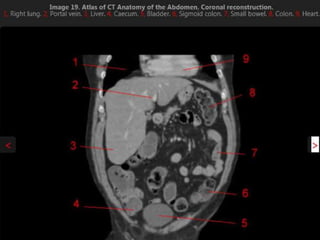

CT cross sectional anatomy.

CT – computedtomography. •Cross-sectional modality with capabilities for multiplanar reconstruction and dynamic imaging to assess vascularity •Tube rotates around the body and a circle of stationary detectors detects the penetrating x-rays forming an image.